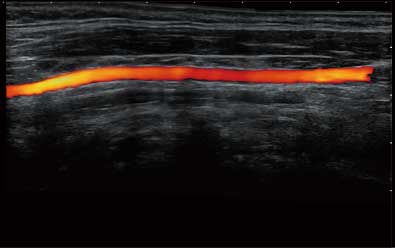

结合百老汇电子游戏官网超宽频带探头技术优势,能够更好地获得高分辨力与高穿透力的平衡,保证图像质量,为临床诊断保驾护航。